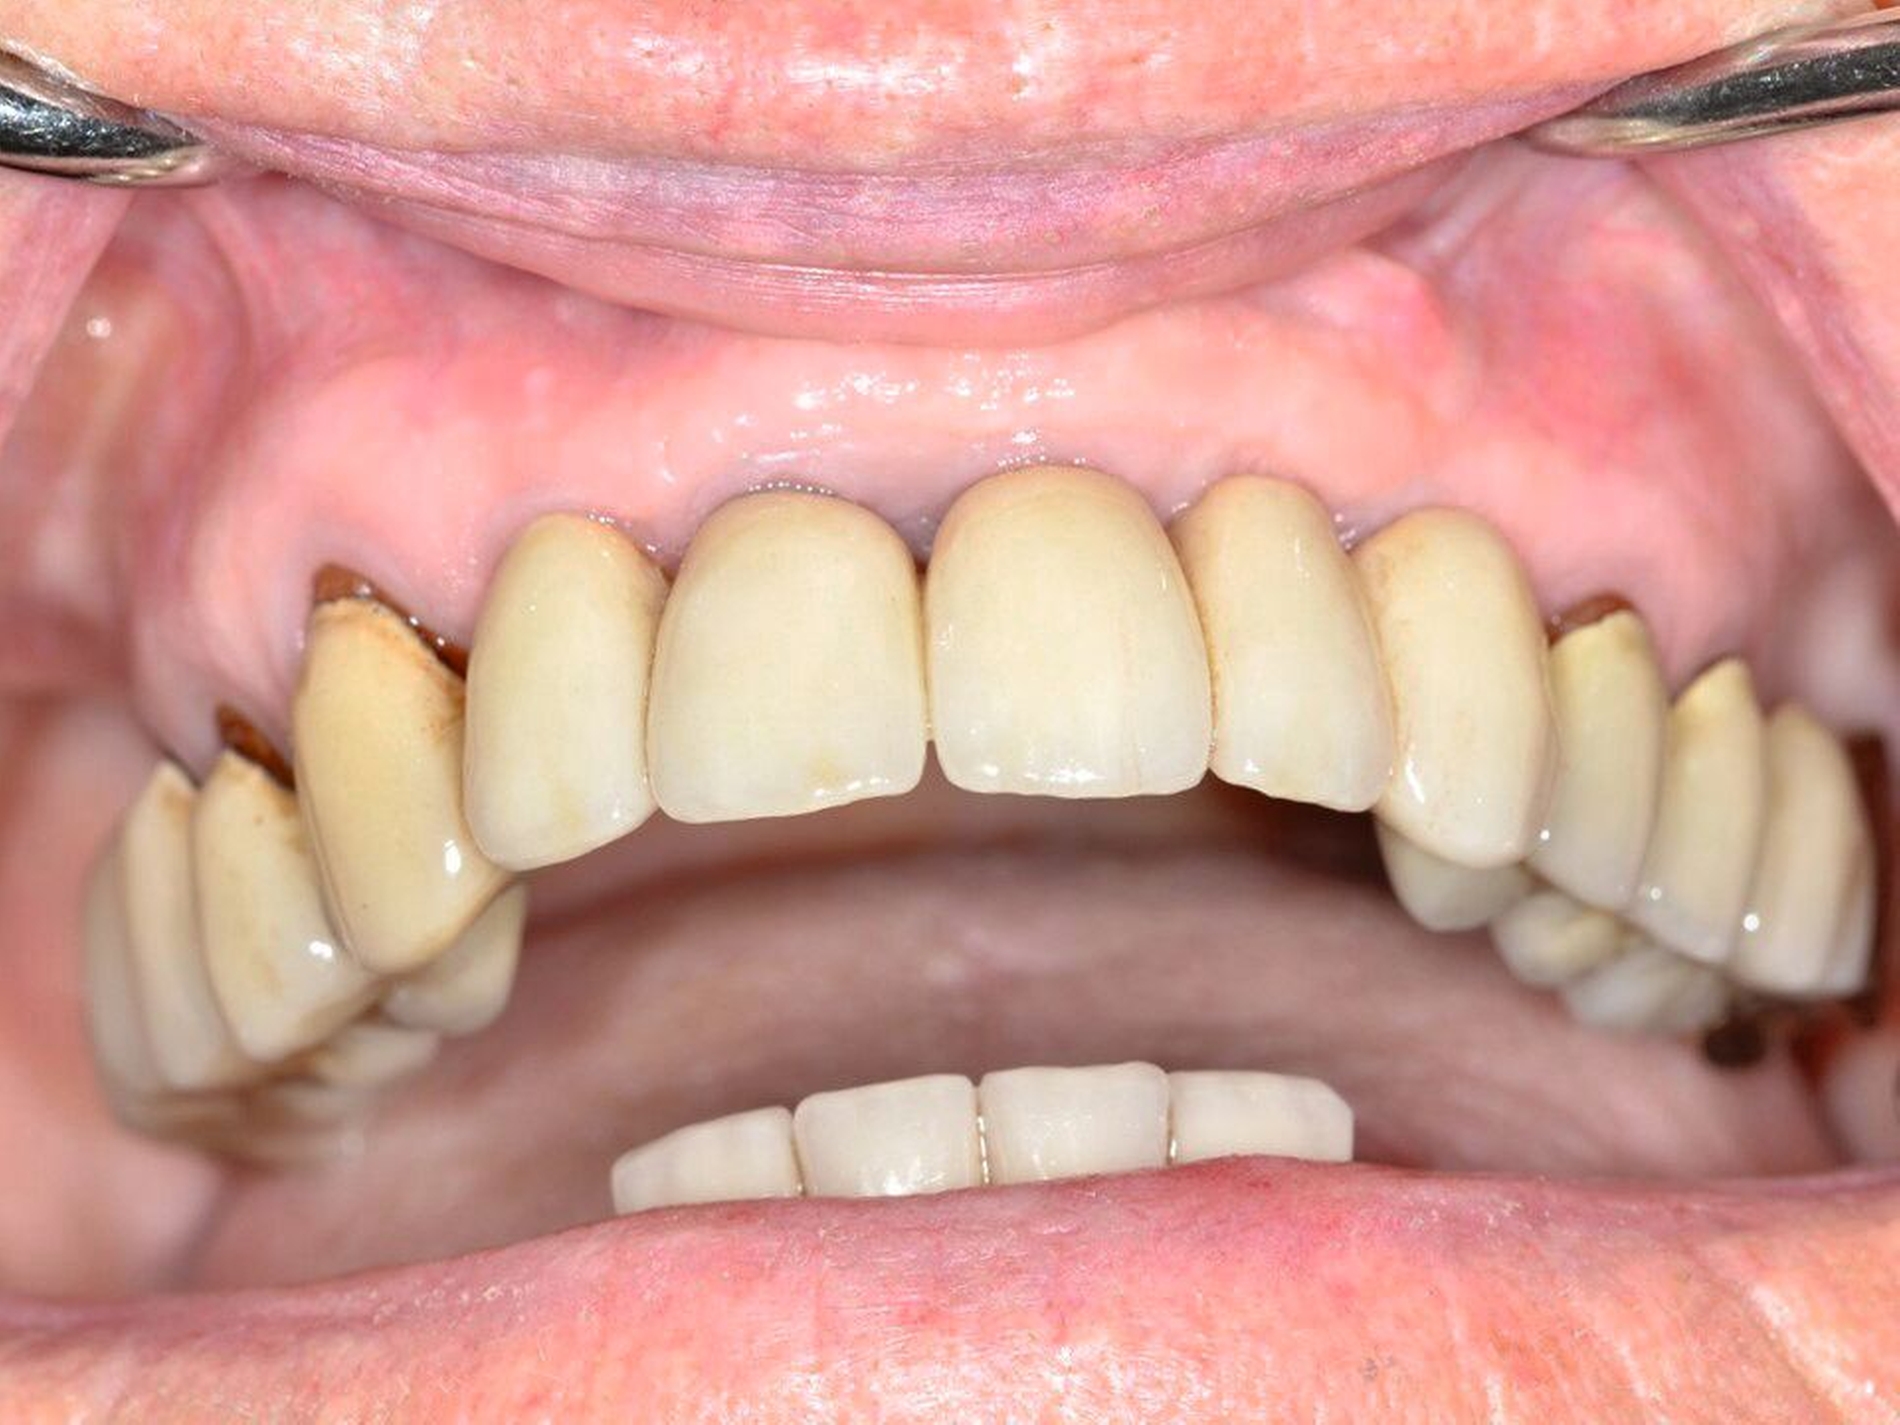

Eine Dekoronation ist eine chirurgische Intervention, die durchgeführt werden kann, wenn aufgrund ausgeprägter Schädigungen der desmodontalen Zellen und der Wurzeloberfläche eine Resorption auftritt. Im Rahmen der klinischen Untersuchung imponiert der betroffene Zahn aufgrund der Ankylose mit einem metallischen (hellen) Klopfschall. Röntgenologisch lassen sich Resorptionslakunen an der Wurzeloberfläche erkennen. Bei progressiver Resorption und Infraposition des betroffenen Zahnes in Relation zur Restdentition kann eine Dekoronation indiziert sein [Malmgren et al., 2015] (Abbildung 2).

Das Ziel der Dekoronation ist es, die klinische Krone unter Belassung der resorbierenden Wurzel zu entfernen, damit der Alveolarknochen aufgrund der Knochenneubildung bei Ersatzresorption erhalten und eine optimale Voraussetzung für spätere Interventionen gegeben werden kann [Malmgren et al., 2006]. Bei Patienten im Wachstum kann die Dekoronation eine sinnvolle Therapieoption darstellen, um den teils erheblichen Knochenverlust in Verbindung mit der chirurgischen Entfernung der ankylosierten Zahnwurzel zu vermeiden (Empfehlung 60).